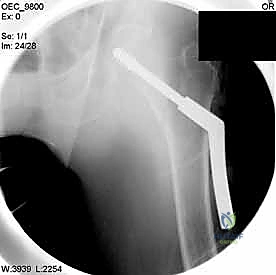

3. الشق الجراحي والنهج الطبي

بناءً على التقنية المختارة (DHS أو PFN)، يقوم الجراح بعمل شق دقيق. في تقنية المسمار النخاعي، تكون الشقوق صغيرة جداً للحفاظ على الأنسجة الرخوة وتقليل النزيف.

5. الحفر وتثبيت الغرسة (Reaming and Implantation)

يتم استخدام أداة حفر مجوفة تمر فوق السلك الدليلي لتوسيع مسار في العظم. بعد ذلك، يتم إدخال المسمار الرئيسي القوي (سواء المسمار المنزلق أو المسمار النخاعي).

6. التثبيت النهائي (Locking)

لضمان عدم تحرك الغرسة، يتم تثبيتها بمسامير إضافية أصغر في جسم عظم الفخذ. هذه المنظومة الميكانيكية توفر ثباتاً استثنائياً يسمح للمريض بتحريك ساقه فور استيقاظه من التخدير.

مجموعة من الصور الإضافية التي توضح مراحل دقيقة من العمل الجراحي المعقد الذي يجريه الأستاذ الدكتور محمد هطيف لضمان أعلى درجات الدقة الميكانيكية الحيوية: